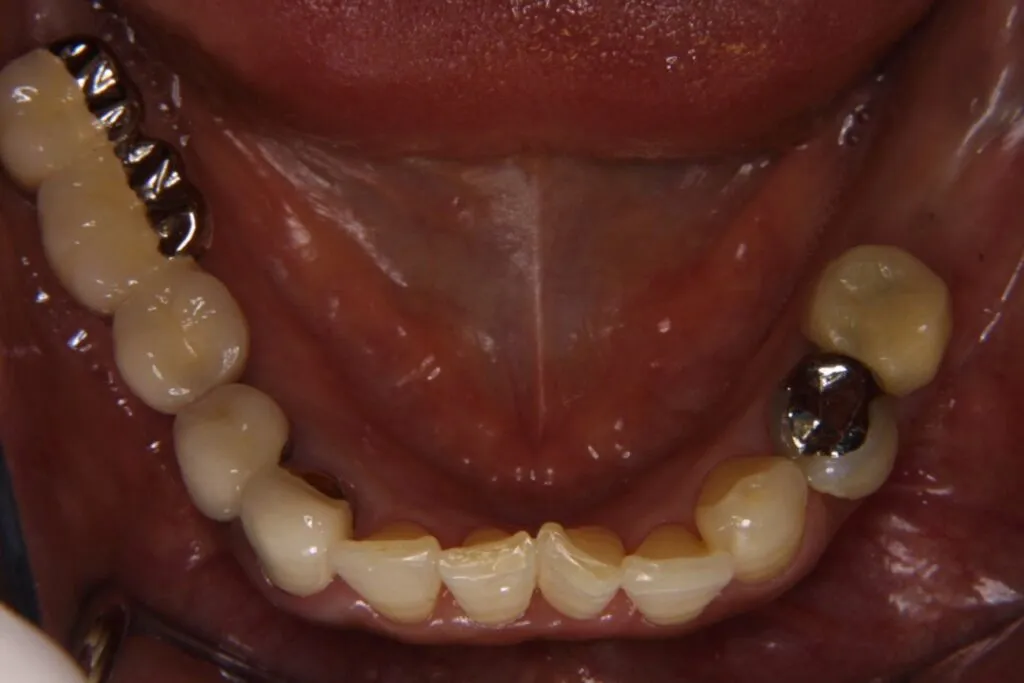

症例⑦

| 主訴 | 残根状態 歯を入れたい |

| 診断名 | 咀嚼障害 |

| 年齢 | 29歳 |

治療に用いた装置(治療法) | インプラント |

| 部位 | 左上6・左上7・左下6・左下7 |

| 治療期間 | 8か月 |

| 治療費用 | 1,848,000円 |

| リスク・副作用(治療に関する) | 腫脹、しびれ |